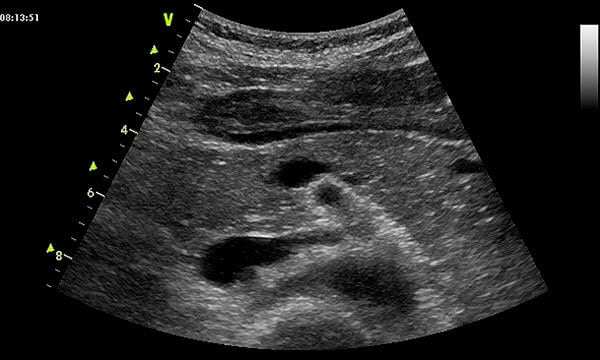

Из-за глубокого расположения органа ультразвуковое исследование считается оптимальным вариантом инструментального анализа. С его помощью можно увидеть кальцификаты в органе, наличие воспалительного процесса железы, а также различные опухоли, новообразования и другие патологии.

Во время процедуры врач чётко определяет размер, форму, расположение и структуру органа. Сравнив с нормальными показателями, выдаёт протокол исследования. После этого пациента направляют к узкопрофильному специалисту, которые поставит грамотно диагноз и назначит лечение при обнаружении патологии. Возможно, потребуются дополнительные анализы и обследования.

В ходе исследования врач оценивает множество параметров, в том числе расположение, размеры, чёткость контуров и структуру железы. Любое отклонение от нормы может указывать на патологию.